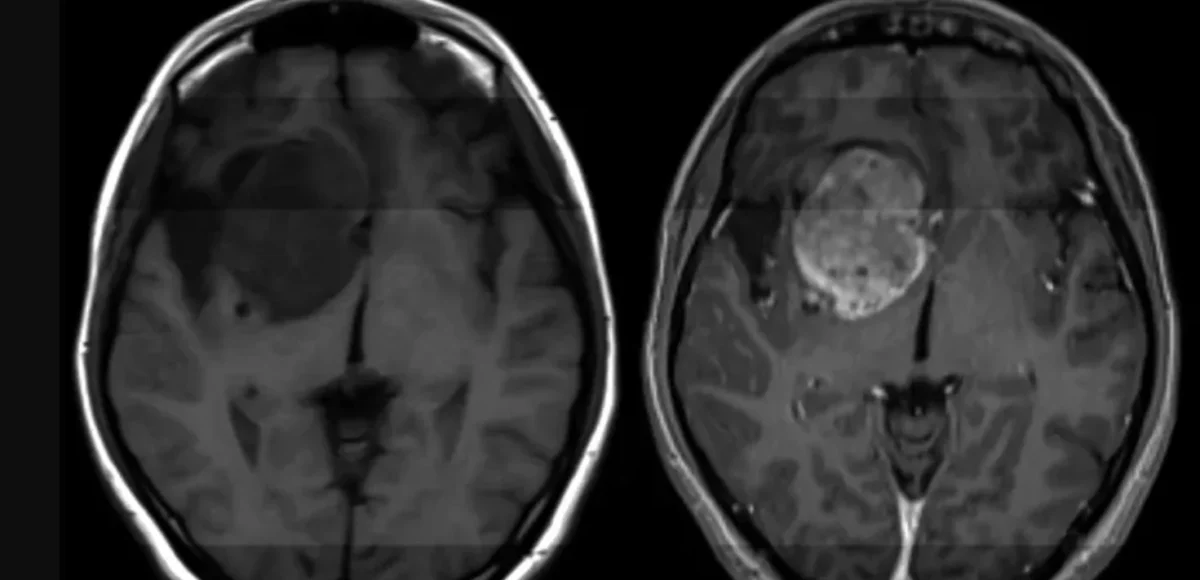

Ας μια άκρως πολύ σημαντική εξέλιξη όσον αφορά την παθολογία του γλιοβλαστώματος, ένας από τους πιο συχνούς καρκίνους του εγκεφάλου για τον οποίο αυτή τη στιγμή δεν υπάρχει κάποιου είδους θεραπεία. Ερευνητές σε επιστημονική δημοσίευσή τους στο Science Translational Medicine, αναφέρουν ότι κατάφεραν να βρουν τρόπο να τον καταπολεμήσουν.

Σύμφωνα με στοιχεία, κάθε χρόνο περισσότεροι από 14.000 άνθρωποι στις ΗΠΑ διαγιγνώσκονται με γλοιοβλάστωμα, ένας επιθετικός, απρόβλεπτος και χωρίς δυνατότητα πρόληψης καρκίνος στον εγκέφαλο.

Καθένας από αυτούς τους νέους ασθενείς στους οποίους γίνεται διάγνωση του εν λόγω καρκίνου θα ζήσει κατά μέσο όρο για 12 με 18 μήνες χωρίς να υπάρχει κάποια θεραπεία και μόλις μία στις 20 περιπτώσεις θα καταφέρει να παραμείνει εν ζωή μετά από 5 έτη.